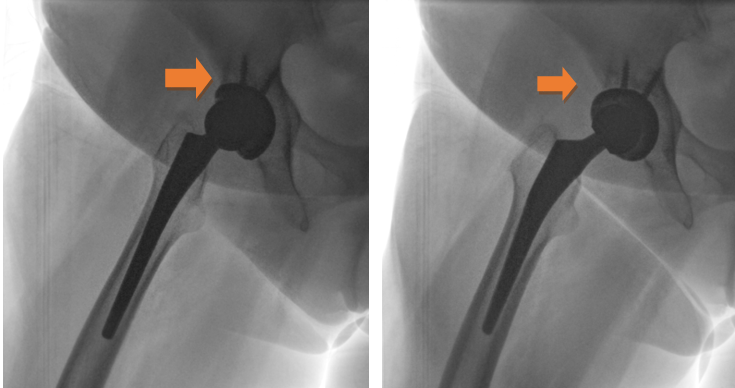

Taking into consideration the short post-operative time, it was decided to avoid any nuclear medicine examination, such as single-photon emission computed tomography (SPECT)-CT or positron emission tomography (PET) to limit the risk of exposure. It is shown that these imaging modalities present lower accuracy in the early post-operative period. Given the fact that there were no signs of infection, early loosening of the THA components was suspected, and so a dynamic radiographic imaging was scheduled to examine the THA prostheses during movement. The examination was undertaken in the radiology department with the equipment of a barium meal gastrointestinal series for high-resolution imaging. The patient was placed in a supine position with the affected limb free and the chest, abdomen, and genitalia of the patient covered with a radioprotective gown. The surgeon passively performed hip flexion, hip extension, internal and external rotation to the extremes of the hip range of motion of the left lower extremity under radiography. The movements were performed in a circular manner, anti-clockwise starting from 60° flexion and internal rotation to full external rotation followed by hip extension. The same movement protocol was followed in 90° flexion and in 100° of hip flexion. Dynamic imaging revealed gross motion of the acetabular cup during passive movements of the hip joint, so the diagnosis of aseptic loosening was established (Fig. 6 and Video 1).

Figure 6: Images during dynamic radiography.

Video 1: Gross motion and instability of the acetabular cup during dynamic radiography.